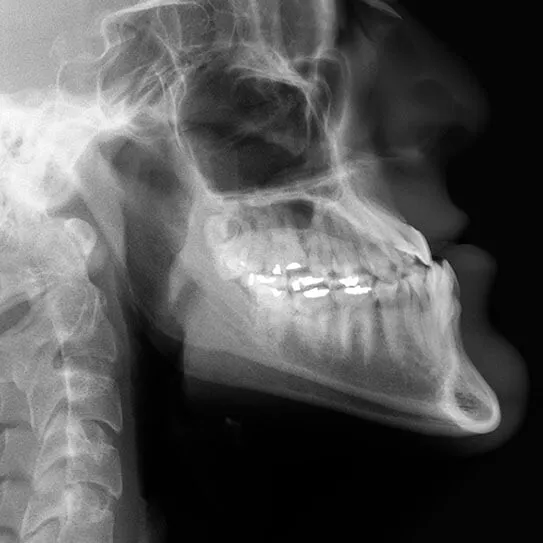

OUR TEETH ARE MEANT to fit together in a specific way. It’s how we are able…